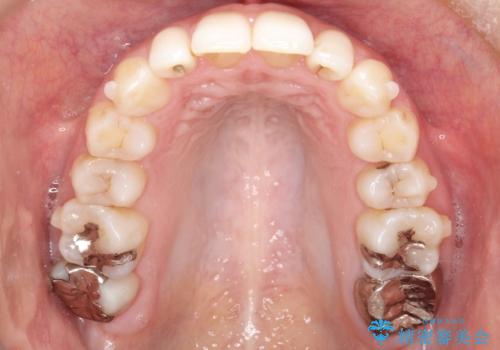

抜歯なし/インビザラインによるマウスピース矯正にて治療を行いました。

内側に入り込んでしまっている歯を出してくることに非常に時間がかかりましたが、一度歯を歯茎の方へ押し込みそして前へ出してくる2段階の治療を行いました。

見た目、嚙み合わせ及び、治療期間や施術内容に大変ご満足いただきました。